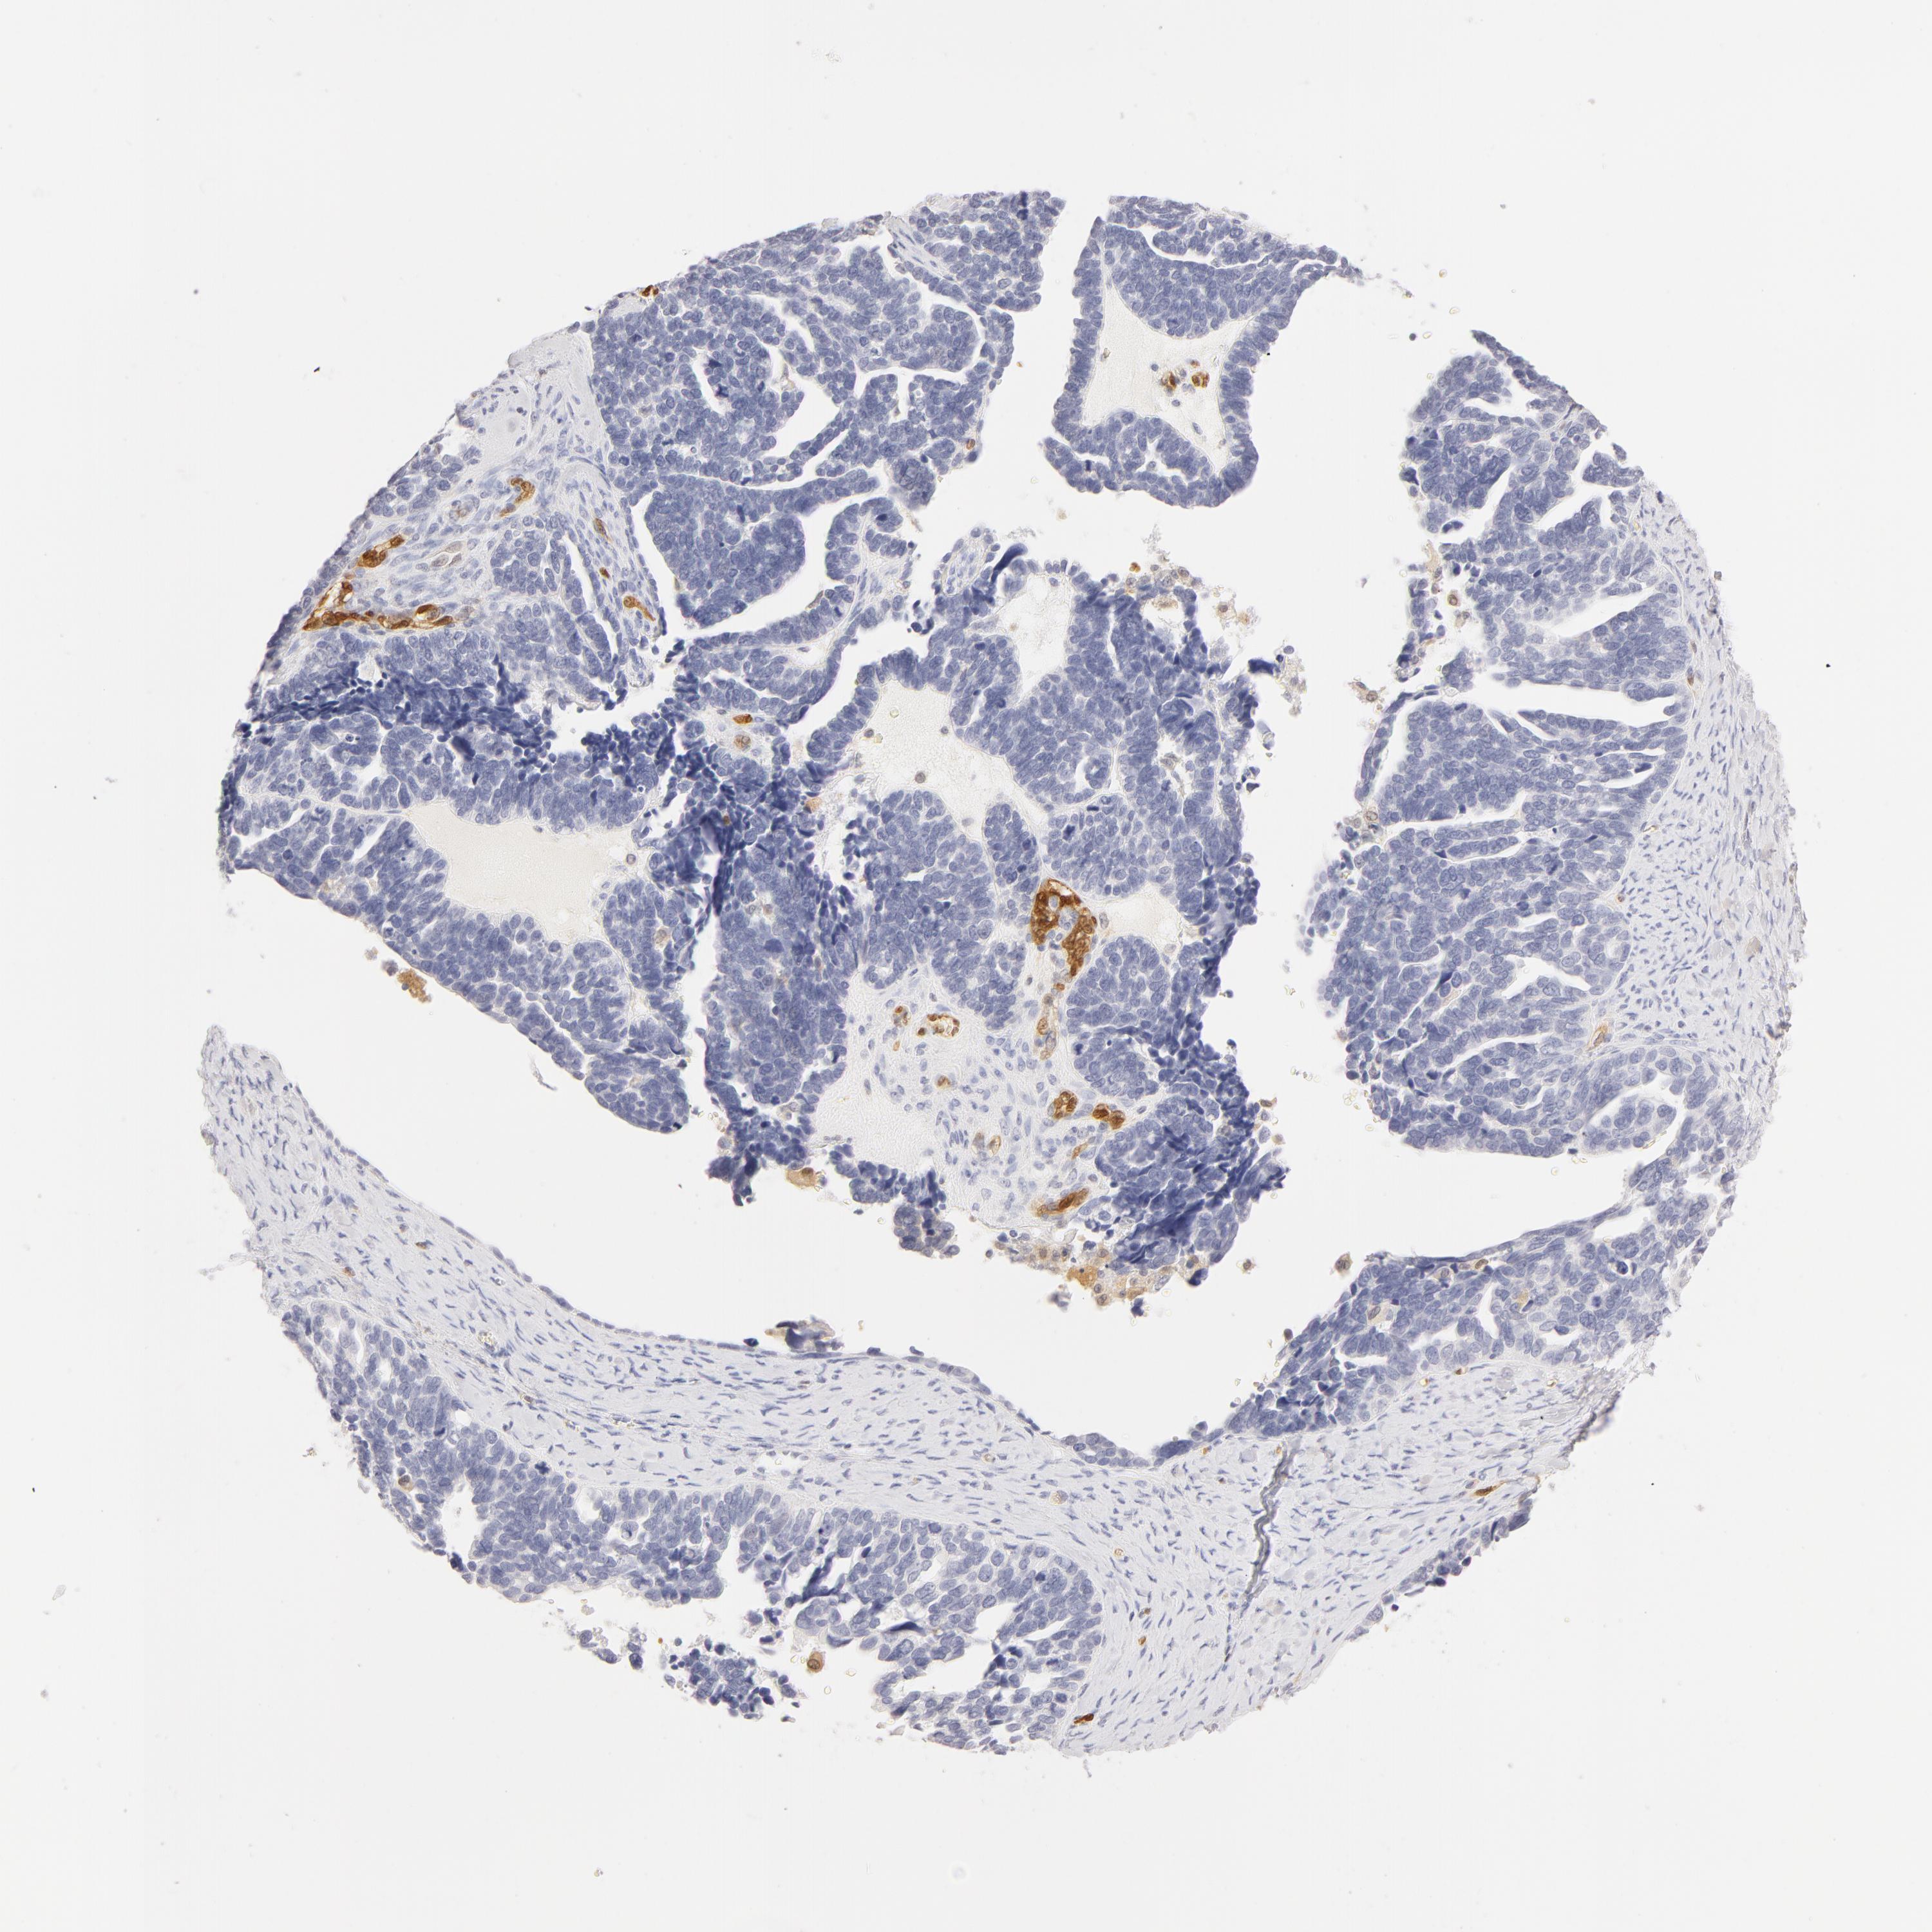

OVARIAN CANCER - Protein expressioni

A mouse-over function shows sample information and annotation data. Click on an image to view it in a full screen mode. Samples can be filtered based on level of antibody staining by selecting one or several of the following categories: high, medium, low and not detected. The assay and annotation is described here.

Note that samples used for immunohistochemistry by the Human Protein Atlas do not correspond to samples in the TCGA dataset.

Antibody stainingi

Antibody staining in the annotated cell types in the current human tissue is reported as not detected, low, medium, or high, based on conventional immunohistochemistry profiling in selected tissues. This score is based on the combination of the staining intensity and fraction of stained cells.

Each image is clickable and will lead to virtual microscopy that enables deeper exploration of all samples and also displays staining intensity scores, fraction scores and subcellular localization as well as patient and tissue information for each sample.

Antibody HPA001550

Antibody CAB010102

Staining

High

Medium

Low

Not detected

Intensity

Strong

Moderate

Weak

Negative

Quantity

>75%

75%-25%

<25%

None

Location

Nuclear

Cytoplasmic/membranous

Cytoplasmic/membranous,nuclear

Carcinoma, endometroid

Cystadenocarcinoma, serous, NOS

Cystadenocarcinoma, mucinous, NOS

Carcinoma, NOS